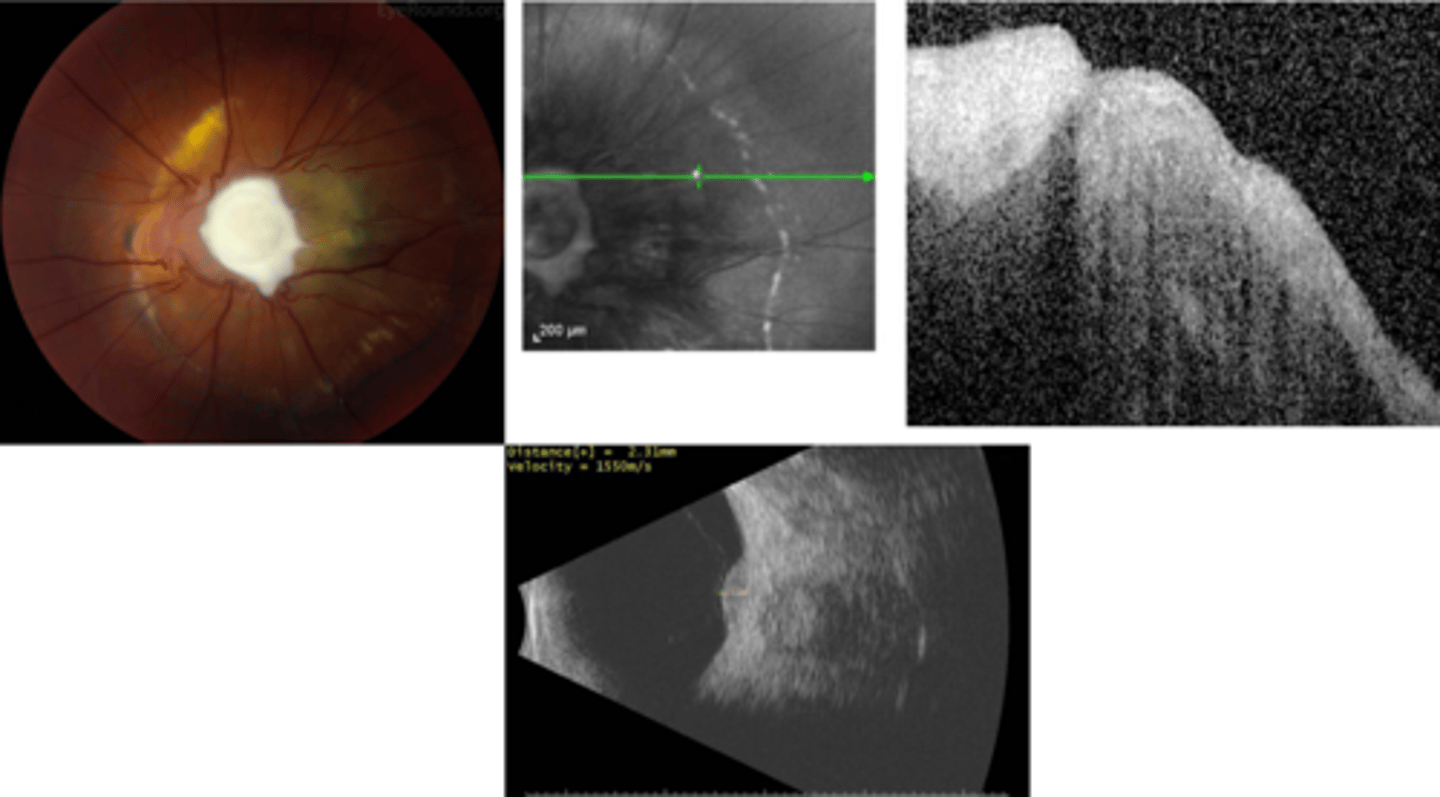

How does ocular toxocariasis appear on OCT, as seen here in patient A?

multiple light granulomas = hyperR

How does ocular toxocariasis appear on OCT, as seen here in patient B?

recurrence = granulomas with exudates, edema

How does ocular toxocariasis appear on OCT, as seen here in patient C?

granuloma now in nasal retina, fibrous memb where granuloma once was (looks like ERM)

How does ocular toxocariasis appear on B-scan here?

granuloma mass over ONH = high-reflectivity